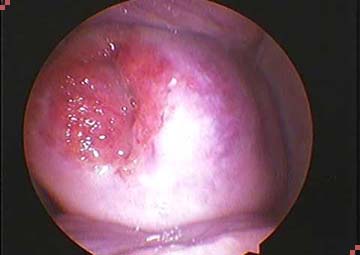

Khi đến phòng khám kiểm tra bằng máy sẽ thấy:

- Lớp biểu mô lẽ ra ở lỗ trong cổ tử cung, nhưng đã lan ra ngoài che phủ một phần cổ tử cung, ở dưới là lớp đệm.

- Có nhiều mạch máu tạo ra hình ảnh một tổn thương có màu đỏ và sần sùi giống như mô hạt.

Quan sát bằng máy sẽ thấy có 2 trường hợp bị viêm lộ tuyến cổ tử cung:

- Lộ tuyến nông là vùng tổn thương có thể xuất hiện trên diện rộng nhưng lớp tế bào liên kết ở bề mặt chưa hết hẳn.

- Lộ tuyến sâu là khi các lớp tế bào đã mất hết, lớp đệm phía dưới lộ hẳn lên bề mặt.

Mức độ viêm lộ tuyến cổ tử cung nặng hay nhẹ được đánh giá thông qua sự tổn thương của tế bào ở mức độ nông hay sâu. Để đánh giá chính xác mức độ tổn thương, cần phải khám và làm xét nghiệm tế bào.

Hình ảnh viêm lộ tuyến cổ tử cung